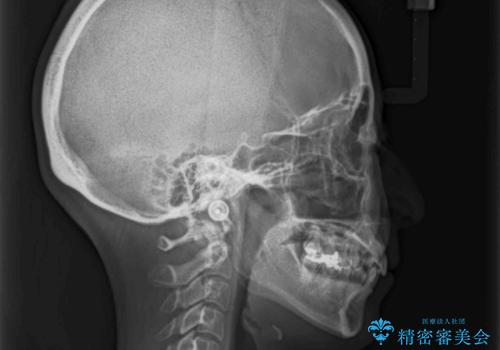

- 下顎の八重歯と、上下のクロスバイトを気にして来院された患者様です。

インビザラインを用い、下顎全体の後方移動、IPR(歯と歯の間を削る)と歯列全体を拡大させることで、歯並びを整えていくこととしました。